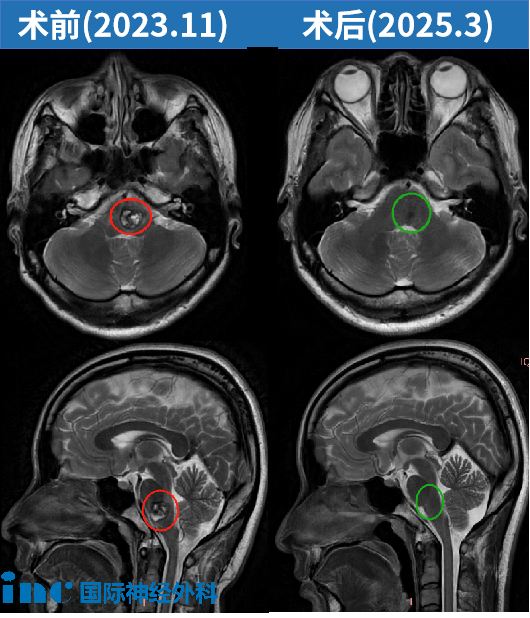

术后3个月:影像复查表示“全切海绵状血管瘤”,琳琳自己也很满意目前的恢复情况。

术后1年4个月:巴教授进行随访,琳琳术后情况非常好,没有残留病灶,也没有出现局部形态学上的负面副作用。